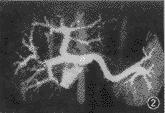

图1 肝右叶肝癌。CTP图像(MPVR)示门静脉和病灶同时清楚显影,门静脉右支受肿瘤(mass)推移,呈抱球状,管壁仍光滑